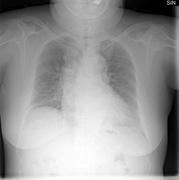

April 20, 2011 – A new study published in Radiology has demonstrated that using a bone suppression application with chest X-rays significantly increased the detection of lung nodules proven to be primary lung cancer. The study used Riverain Medical’s SoftView system. SoftView enhances chest imaging uses machine learning and image processing algorithms to suppress the ribs and clavicles that obscure nodules that may be early-stage lung cancer. The reader study, funded by Riverain Medical and conducted at Georgetown University in Washington, D.C., was led by Matthew Freedman, M.D., associate professor of Oncology at the Lombardi Comprehensive Cancer Center. The study consisted of fifteen radiologists analyzing 368 chest X-rays. The radiologists interpreted the standard chest X-ray to locate lung nodules and then reviewed the SoftView bone suppressed image. The authors concluded that “the radiologists using visualization software significantly increased their detection of lung cancers and benign nodules" than without this technology. In fact, 74 percent of the additional cancers found when reviewing the SoftView images were in hard-to-view areas with 70 percent or greater bone and nodule overlap. As a result, the program helped clinicians decide whether to suggest additional diagnostic testing including CT and lung biopsy. “Finding lung cancer at its earliest, most treatable stage is the key to the survival of this disease that claimed the lives of more than 150,000 Americans in 2010 alone,” said Steve Worrell, chief technology officer of Riverain Medical. “The publication of this peer-reviewed study confirms that SoftView allows physicians to identify more early-stage lung nodules under some of the most challenging conditions when using a chest X-ray.” The U.S. Food and Drug Administration (FDA) cleared the application in March 2010. , It is designed to increase the clarity of chest X-rays by suppressing bone. It can be applied to every chest X-ray in the hospital without specialized imaging equipment, changes in imaging protocols or additional radiation dose to the patient. Using advanced bone suppression and image enhancement algorithms, it automatically provides a soft tissue image for more confident image interpretations. “Clinical data has shown that the early detection of lung cancer can save lives,” said Diane Hirakawa, CEO and chairman of Riverain Medical. “It is encouraging to see a growing body of scientific work demonstrating the benefits of SoftView. Riverain Medical is committed to developing technology that can change the outcomes of patients by aiding in the detection of cancer at its earliest and most treatable stage.” For more information: www.rivertainmedical.com